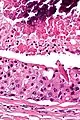

Their histologic appearance is similar to ductal breast carcinoma.

Intermed. mag.